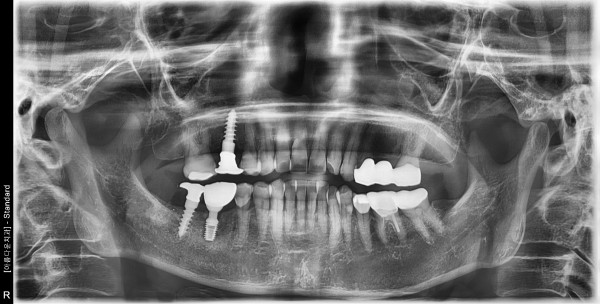

57세 여자 하악 우측 구치부 발치, 치조골이식술 후 임플란트 식립